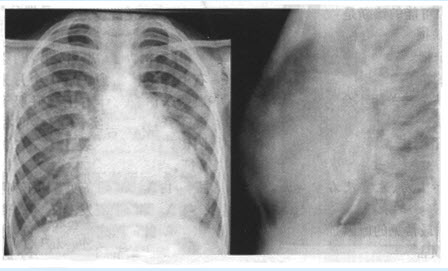

患者,男,22岁。乏力、倦怠2年余,半年前出现活动后气促。查体:心尖区可闻及收缩期高调吹风样杂音。X线胸片如下图所示。

(多选题)对上图所见描述正确的是()

A:右房增大

B:左房增大

C:右室增大

D:左室增大

E:心腰突出

F:右房右室增大